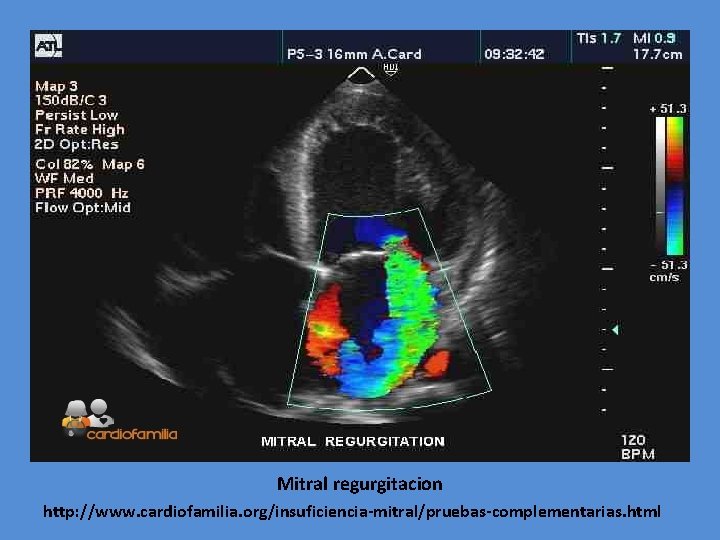

Eco bidimensional y doppler color en posición apical 4 cámaras: Dilatación importante de cavidades izquierdas, VM engrosada, y jet excéntrico de IM. Divisão de Cardiología Pediátrica e Ecocardiografía Pediátrica do Instituto do Coração, Hospital das Clínicas, Facultade de Medicina de São Paulo, Brasil

Mitral regurgitacion http: //www. cardiofamilia. org/insuficiencia-mitral/pruebas-complementarias. html